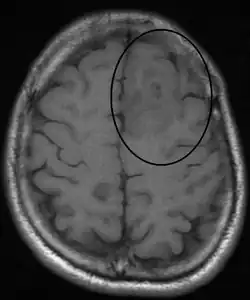

An oligodendroglioma as seen on MRI